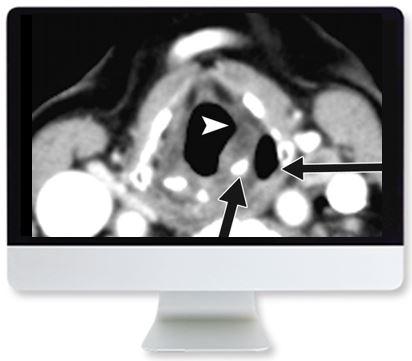

This Online Course reviews thyroid cancer epidemiology, risk stratification, and imaging and therapy guidelines—including indications, challenges, and controversies for both adult and pediatric patients. A practical approach to imaging and therapy in patients with thyroid cancer, participants will complete this course acutely aware of current questions and ongoing debates, as well as available data used to address them.